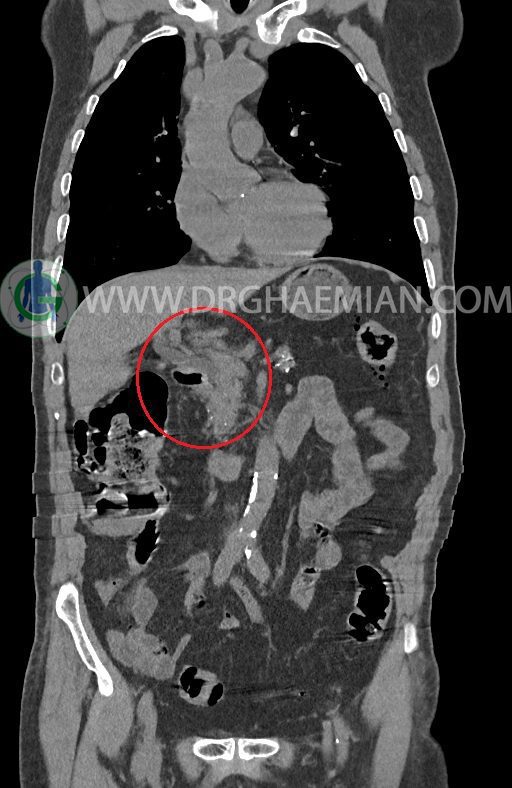

در سی تی اسکن اسپیرال ریه ها و مدیاستن، شکم و لگن با و بدون کنتراست وریدی (مولتی دیدکتور 16 با مقاطع ظریف و بازسازی کرونال) :

–افزایش ضخامت تومورال دیستال مری و GEJ در سگمانی به طول 4cm-5cm (T2 or T3)

-3 لنف نود رژیونال با SAD ≤ 9 mm دیده می شود. (N2)

–آتروفی نسبی پانکراس همراه با فوکوس های کلسیفیه ی منتشر پارانشیم مطرح کننده ی پانکراتیت مزمن

-CBD بسیار دیلاته (16mm) همراه با دیلاتاسیون مجاری داخل کبدی سنترال بدون شواهد سنگ یا توده در مسیر